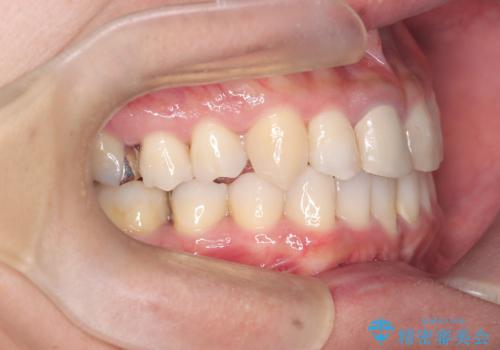

【インビザライン】八重歯と歯のでこぼこが気になる!

- 「八重歯と歯のでこぼこを治したい」を主訴に来院された患者様です。

歯は抜かずに奥歯の遠心移動とIPRで八重歯とでこぼこを改善しました。